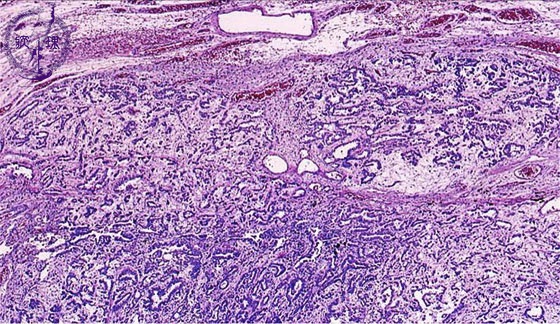

Microscopic view (HE stain, low power view): This mesothelioma has a tubulo-papillary structure with abundant stroma.